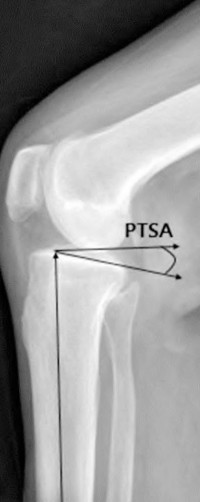

A 65-year-old woman with painful knee arthritis and the deformity seen in Figure A, is scheduled to undergo a total knee arthroplasty. All the following are risk factors for a post-operative peroneal palsy EXCEPT:

Figure A demonstrates and AP radiograph of the knee showing end-stage arthritis with severe lateral compartment narrowing.